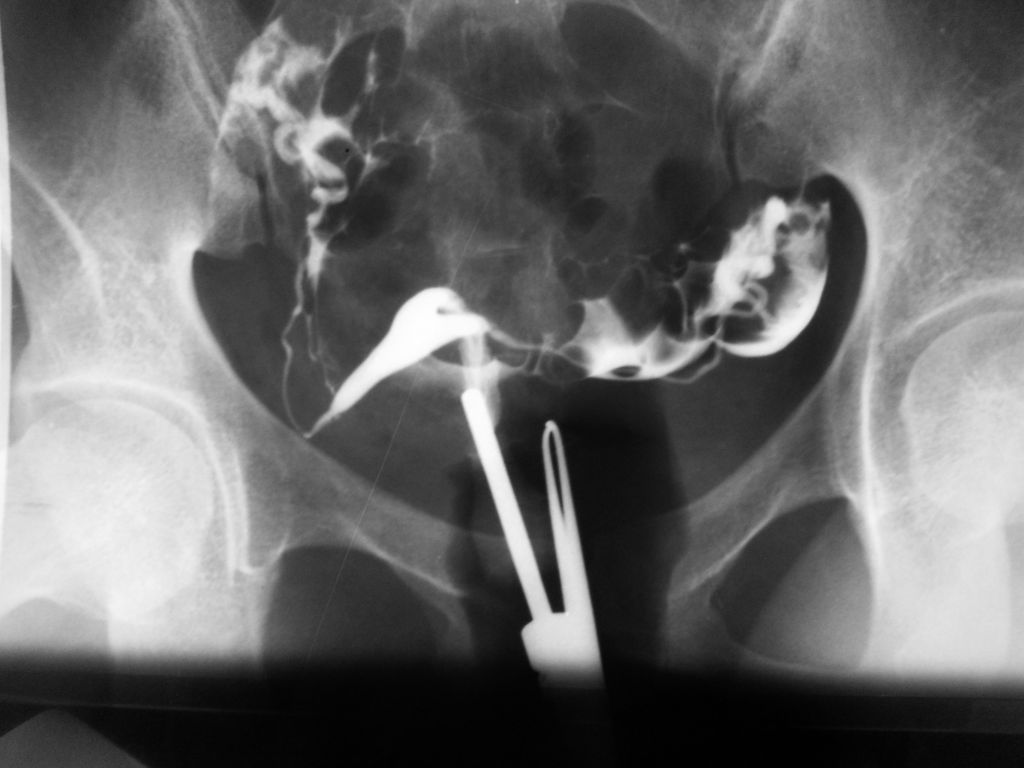

3) Exames contrastados do aparelho urinário como urografias e uretrocistografias.

4) Histerossalpingografia - ótimo método para pesquisa de patologia da cavidade uterina e verificação da permeabilidade tubária, fundamental nos casos de esterilidade conjugal.